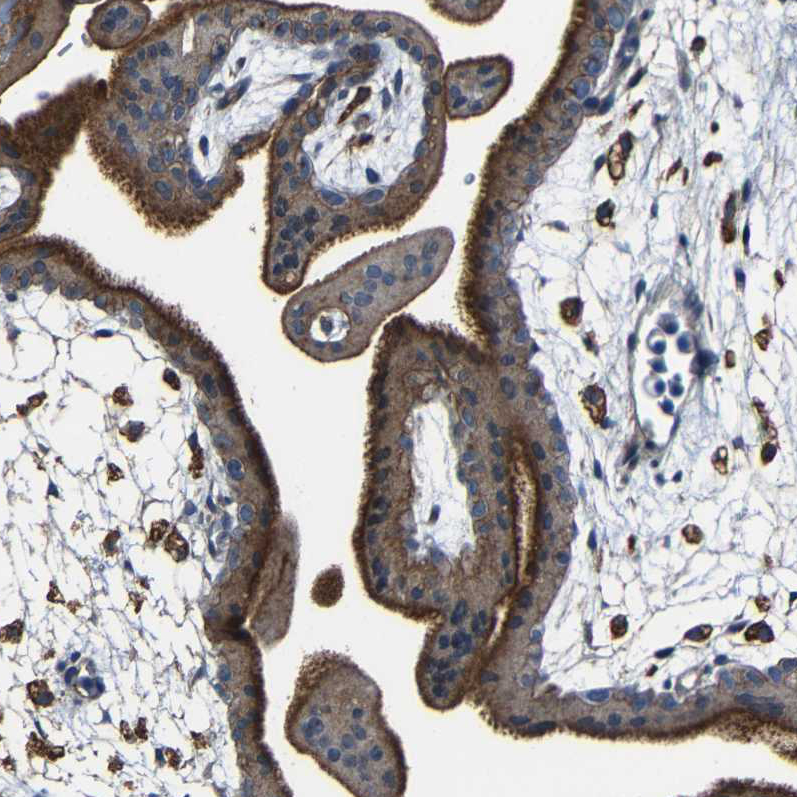

Immunohistochemical staining of human cerebral cortex shows strong positivity in neuropil.